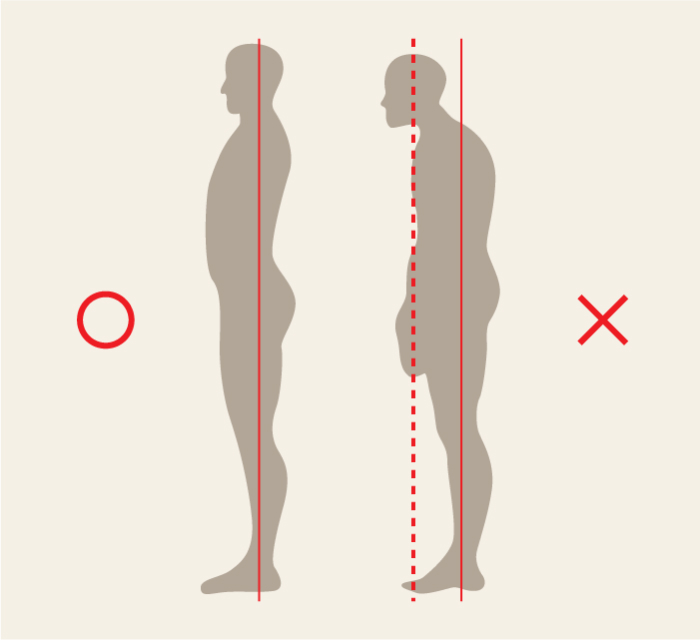

前方頭位

上位交差性症候群

前方頭位

上位交差性症候群

-

頭や肩が前に出て、背中が丸くなっている姿勢